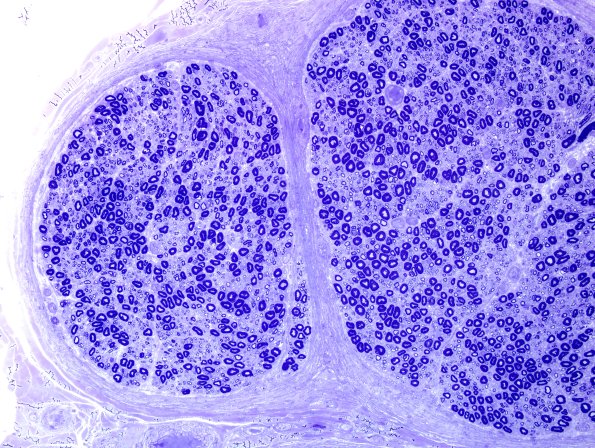

Washington University Experience | PERIPHERAL NEUROPATHY | 1 NORMAL NERVE ANATOMY | 3 Normal Plastic Sections | 3A2 Nearly Normal Nerve, pi granules (Case 3) Plastic 19.jpg

Multiple fascicles at several magnifications showing normal axonal populations.